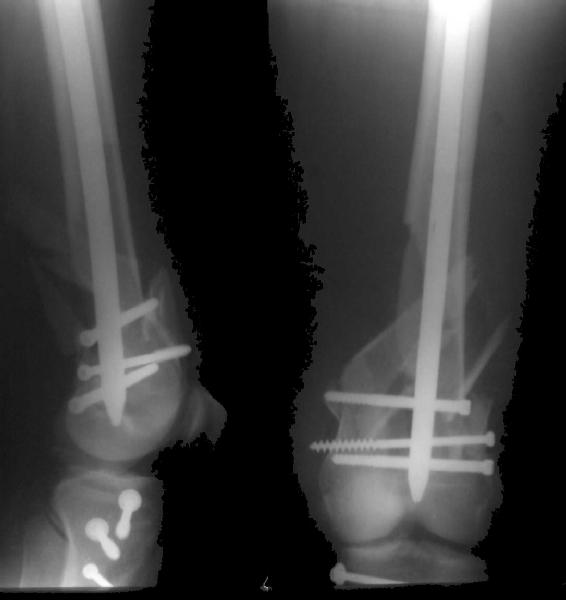

Re: Open supracondylar femur fx

And why LISS is superior here than nail?

Look what we would have done.